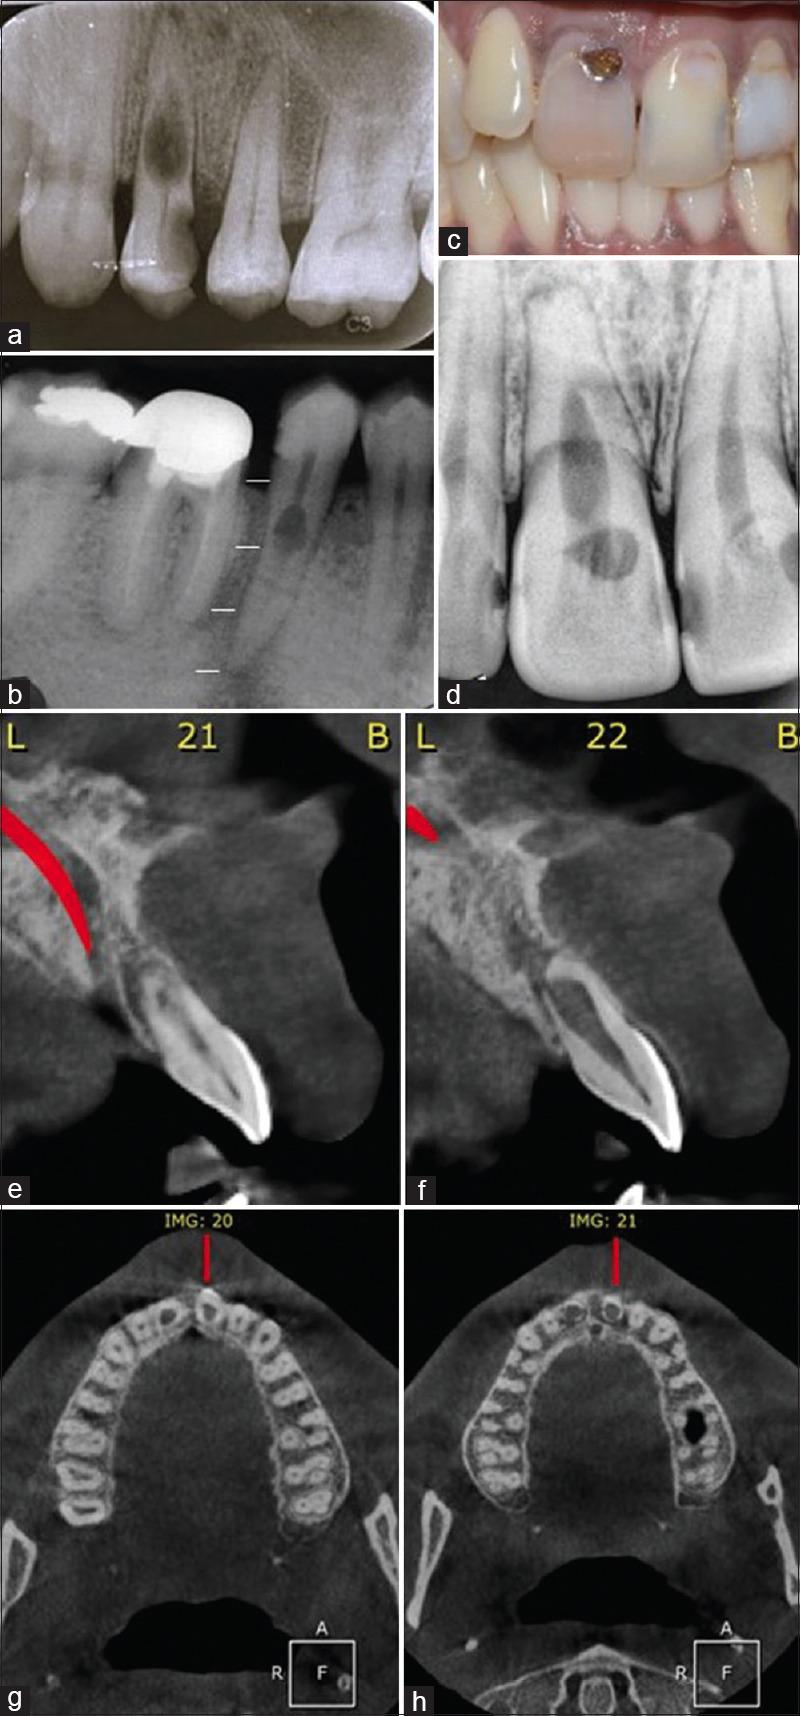

重新定义空洞:一种人类牙齿内部吸收的新分类。

Redefining the void: A novel classification for internal resorption in human teeth.

INTRODUCTION

Internal root resorption is the loss of hard tissue of the tooth from the pulpal surface of the root canal space. This pathologic condition is characterized by damage to the organic sheath, loss of predentin, and odontoblastic layer leading to demineralization of hard tissue of the tooth.

The aim of this article is to classify internal resorptive lesions to distinguish the extent of resorption at various levels as seen in the tooth.

Internal resorption is less commonly diagnosed as compared to external resorption. Internal inflammatory resorption has been classified depending on the inflammatory process of the tooth as transient or persistent. There is a need for classification of the extent and location of the resorptive lesion. Hence, this article is focused on the classification of internal resorption based on the location of the resorptive site and the extent of tissue involved.

牙根内吸收是指根管空间牙髓面的牙齿硬组织丧失。这种病理状况的特征是有机鞘受损、前期牙本质丧失以及成牙本质细胞层受损,从而导致牙齿硬组织脱矿。

本文的目的是对牙根内吸收性病变进行分类,以区分在牙齿中不同层面所见的吸收程度。

与牙根外吸收相比,牙根内吸收的诊断较少见。根据牙齿的炎症过程,将内炎性吸收分为短暂性或持续性。需要对吸收性病变的范围和位置进行分类。因此,本文重点基于吸收部位的位置和受累组织的范围对牙根内吸收进行分类。